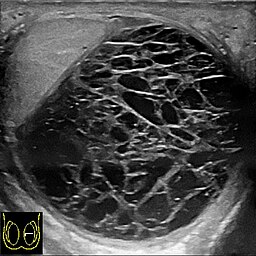

Krwiak lub obrzęk: Najczęstszą przyczyną jest krwiak, czyli nagromadzenie krwi w wyniku uszkodzenia naczyń krwionośnych podczas operacji. Może to także być obrzęk wynikający z reakcji organizmu na uraz operacyjny (to występuje z największym prawdopodobieństwem; można potwierdzić w badaniu USG; obok na zdjęciu tak wygląda krwiak w USG).